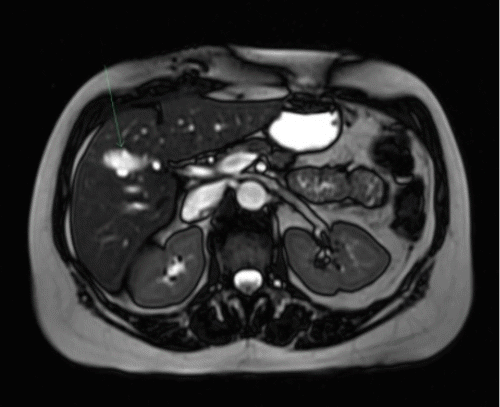

The final examination of the surgical pathology demonstrated chronic cholecystitis with cholelithiasis. Due to potential malignancy concerns within the intrahepatic choledochal cyst, a magnetic resonance cholangiopancreatography (MRCP) was performed two months following the cholecystectomy. This subsequent imaging revealed an anomalous finding—a fusiform dilatation of a specific right intrahepatic duct. This dilated duct drained a portion of segments 4B and 5 directly into the remnant of the cystic duct (Figures 1B and 1C). Notably, to the authors' knowledge, this is the first documented instance of such anomalous drainage of an intrahepatic choledochal cyst. The patient remained free of biliary symptoms one year after the index operation.

B) MRCP demonstrates dilated intrahepatic ducts draining segments 4B and 5 (IH 4B/5) into the remnant of the cystic duct (R-CD) following cholecystectomy.